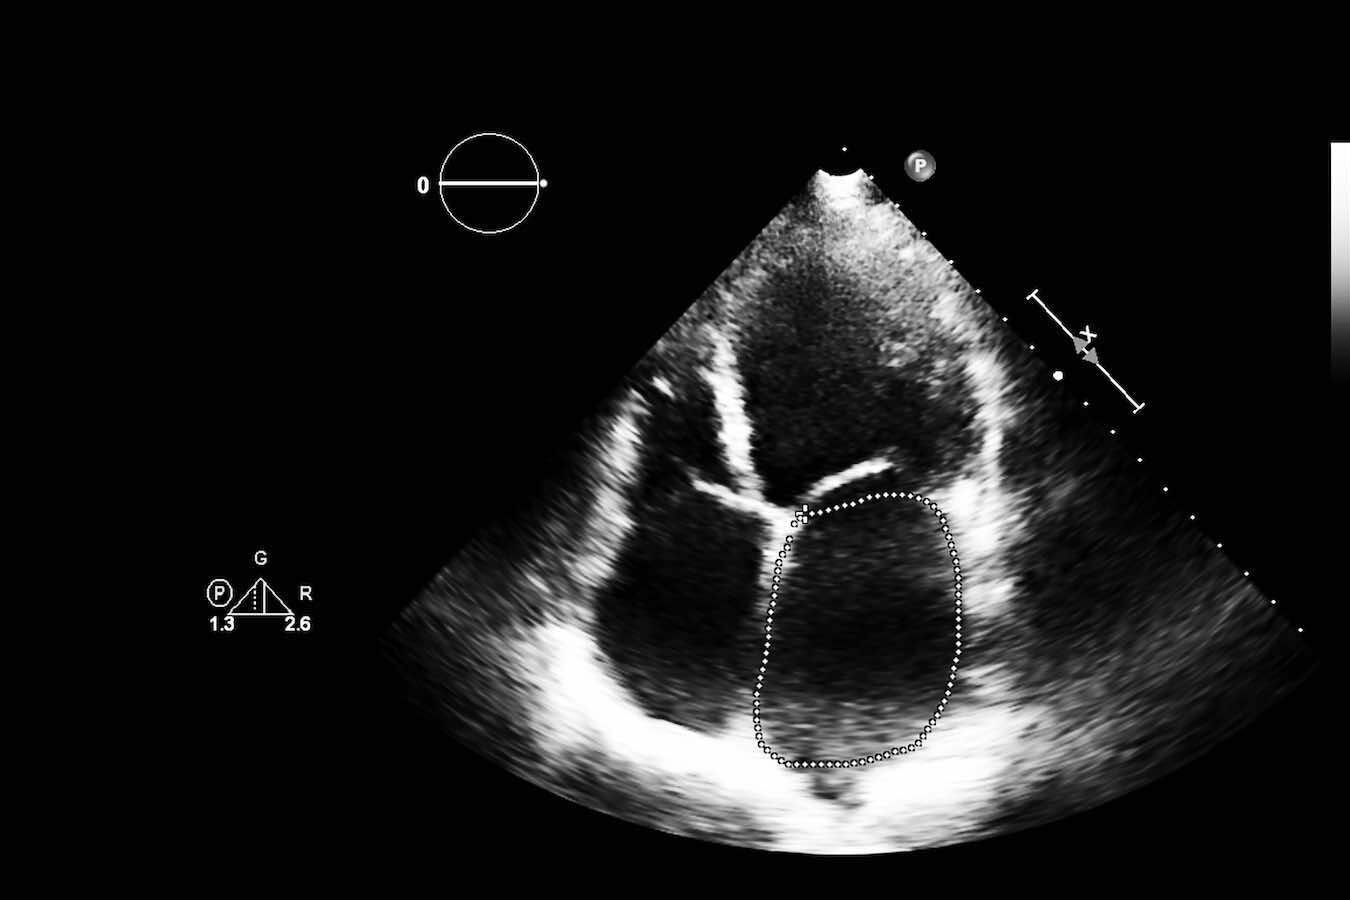

Die Kardiologie ist die Lehre vom Herzen und seinen Erkrankungen. Bei KardioPro bieten wir eine umfassende Bandbreite an diagnostischen Verfahren, um die Funktion und Struktur Ihres Herzens präzise zu beurteilen. Dazu gehören unter anderem das Ruhe- und Belastungs-EKG, der Langzeit-EKG zur Detektion von Herzrhythmusstörungen, sowie der Herzultraschall (Echokardiographie) zur Beurteilung der Herzklappen und der Pumpleistung.